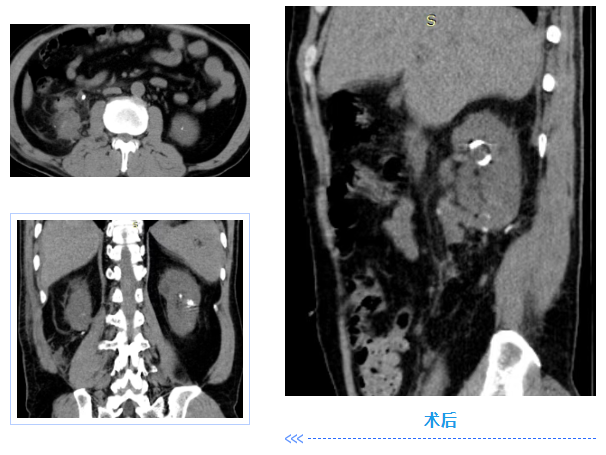

由于肾下极位置特殊,手术不仅要求医生在腔镜下具备精准的判断与定位能力,还需掌握娴熟的病灶切除及组织缝合技术。在泌尿外科与麻醉科的通力协作下,顺利切除了包含结石的肾下部。术后患者恢复良好。

“此次手术是医院腹腔镜技术水平的重要体现,手术难度极大,十分考验医生的专业技术——肾下极切除术需要在肾血流阻断后的极短时间内完成病灶切除与肾盏、肾实质的缝合。手术顺利完成,既依托于科室成熟的专业技术,更是医院团队协作的成果。”罗洪星术后表示。